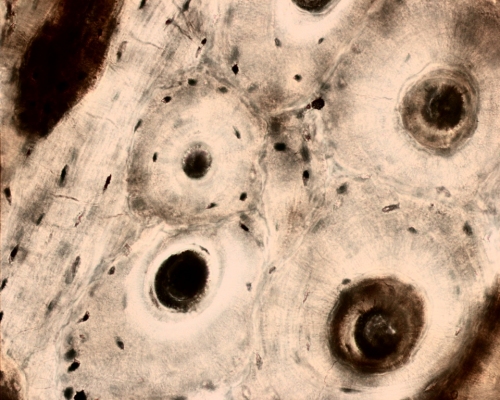

Fig 013-003

Ground section of bone

© augustus 202 marius loots